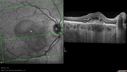

SPECTRALIS-SD-OCT SCAN: The OCT scan of the macula in the right eye does show pigment epithelium thickening, predominately inferior to the fovea where the neovascular complex is with some retinal edema there and subretinal fluid centrally. There is also excrescences off of the pigment epithelium where the white spots are, many of which are under the subretinal fluid, but there is some away from it as well. These appear to indent the small spots which are tiny, roughly 150 microns across, do appear to displace all the layers of the retina, including the external limiting membrane and the other outer lines of the retina and appear to be internal to the basement membrane of the choriocapillaris. It doesn’t appear like there is any choroidal involvement on the OCT scan. The scan of the left eye similarly shows no intraretinal or subretinal fluid. There are however, the deposits which appear to be deep pigment epithelium, but superficial to the basement membrane of the choriocapillaris putting them somewhere in the middle of Bruch’s membrane.